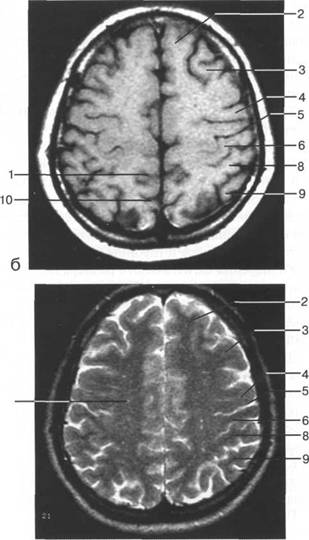

теменно-затылочная борозда; 11 - семиовальные